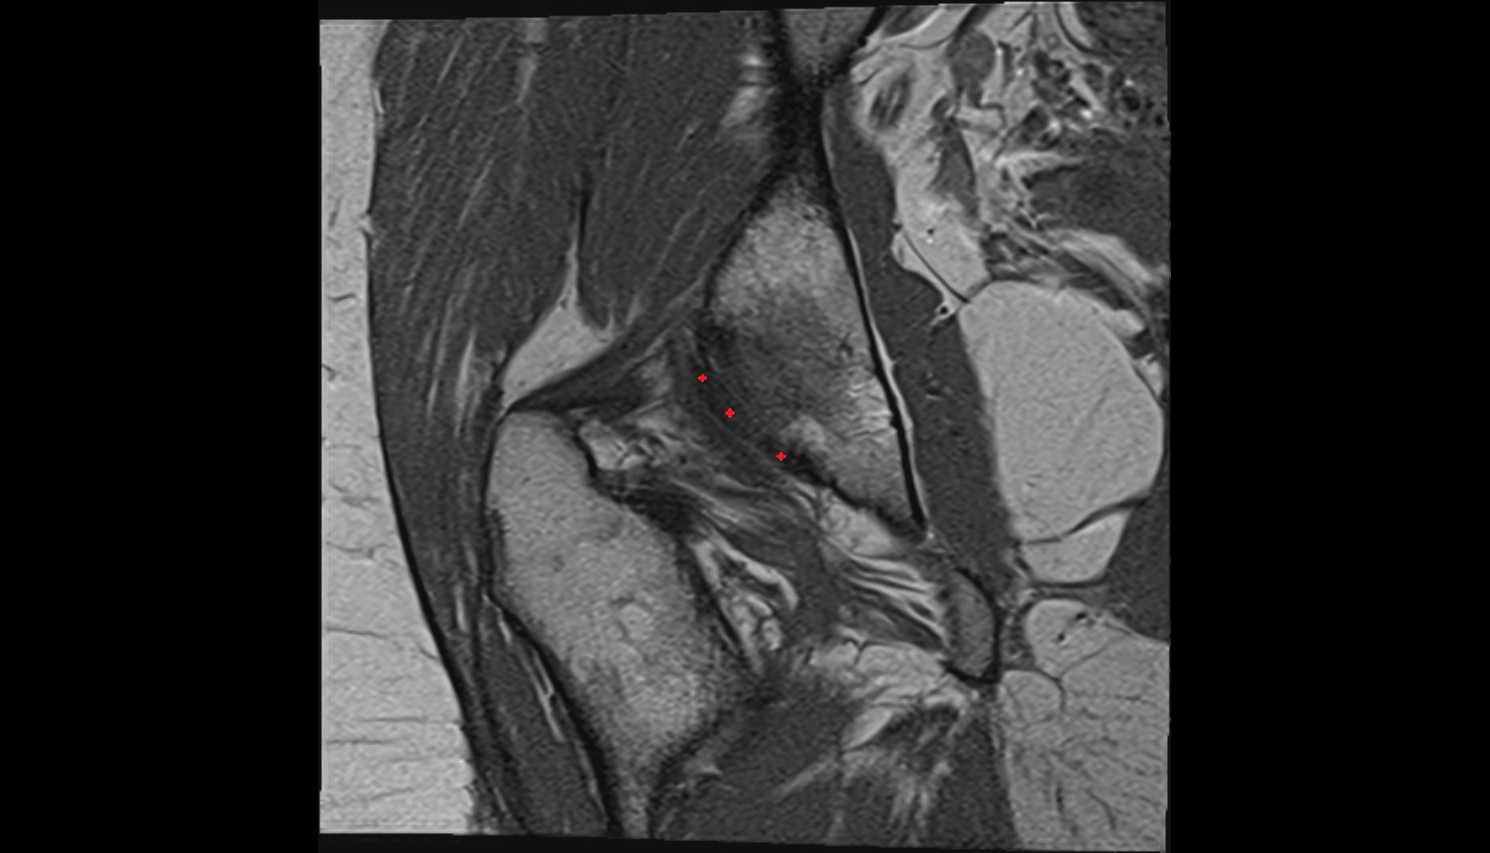

- Hip joint